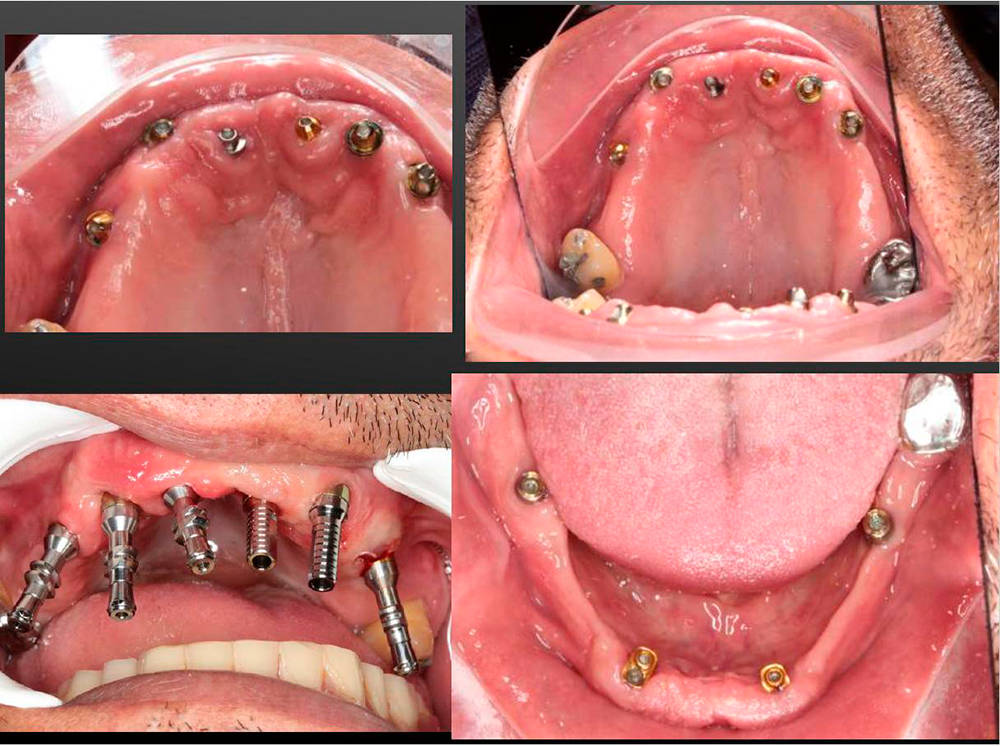

The wide range of DSI prosthetic parts gives the surgeon the freedom to find the ideal solution for every case.

Here is a perfect example - the removable denture based on the Premium Spiral Implants with a strong multi-unit anchoring the full upper overdenture.

The lower jaw is reconstructed by using the Lock-attachment system. Full restoration was created in a previos visit of the patient